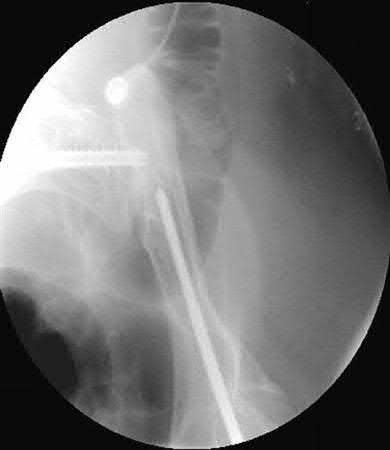

In the treatment of unstable intertrochanteric femur fractures with a cephalomedullary nail, achieving correct lag screw placement is critical. According to the original study by Baumgaertner et al., what is the ideal tip-apex distance (TAD) recommended to minimize the risk of lag screw cut-out?

Options:

Correct Answer: Less than 25 mm

Explanation:

Baumgaertner et al. defined the tip-apex distance (TAD) as the sum of the distance from the tip of the lag screw to the apex of the femoral head on both AP and lateral radiographs, after correcting for magnification. A TAD of less than 25 mm was shown to significantly correlate with a minimal risk of lag screw cut-out in the treatment of intertrochanteric fractures.